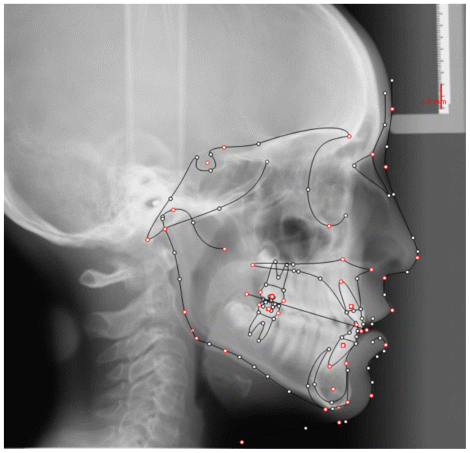

The patient was a young female presenting with a Class III dento-skeletal malocclusion, which was treated using the AMCOP® TC appliance. A comprehensive diagnostic protocol was carried out both before and after treatment, including orthopantomography (Figure 2–3), postero-anterior teleradiography (Figures 4, 5), latero-lateral cephalometric radiography (Figures 6, 7), cephalometric analysis (Tables 1, 2), as well as extraoral (Figures 8, 9) and intraoral photographs (Figures 10, 11). The extraoral examination revealed an edge-to-edge incisal relationship and the presence of a midline diastema. Pre-treatment cephalometric analysis (Deltadent® Lana, Bolzano, Italy) confirmed the diagnosis of a skeletal Class III malocclusion. The treatment plan involved the use of the AMCOP® TC appliance. The patient was instructed to wear the device for two hours in the afternoon and throughout the night for the first six months, followed by nighttime use only for an additional six months. Upon completion of the treatment, the patient achieved a Class I occlusion, with correction of both overjet and overbite. Additionally, the device facilitated tongue re-education and contributed to the postural realignment of the first cervical vertebra.

| Cephalometric Analysis before Treatment | Values (°) | Normal Values (°) |

|---|---|---|

| SNA | 81,3 | 82 ± 3 |

| SNB | 82,9 | 80 ± 3 |

| ANB | −1,6 | 2 ± 2 |

| OVJ | 3.5 | 3.5 ± 2,5 |

| OVB | 0.6 | 2 ± 2,5 |

| CoGoMe | 136,0 | 128,8 ± 4 |

| Is^Ans-Pns | 126,4 | 110 ± 6 |

| Li^GoGn | 106 | 94 ± 7 |

| Apg-Li | 3,6 | 2 ± 2 |

| Cephalometric Analysis after Treatment | Values (°) | Normal Values (°) |

| SNA | 83,0 | 82 ± 3 |

| SNB | 84,0 | 80 ± 3 |

| ANB | 1,0 | 2 ± 2 |

| OVJ | 2,5 | 3.5 ± 2,5 |

| OVB | 1,5 | 2 ± 2,5 |

| CoGoMe | 128,0 | 128,8 ± 4 |

| Is^Ans-Pns | 115,4 | 110 ± 6 |

| Li^GoGn | 99,7 | 94 ± 7 |

| Apg-Li | 2,0 | 2 ± 2 |